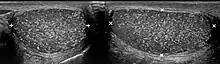

The cause is unknown, but this condition has been associated with testicular cancer in a small group of individuals, cryptorchidism, mumps, infertility and intraepithelial germ cell neoplasia. Classic testicular microlithiasis is defined as five or more echogenic foci per view in either or both testes, and limited testicular microlithiasis defined as one or more echogenic foci that do not satisfy the criteria for classic testicular microlithiasis. In 80% of cases, both testicles are affected.

Testicular ultrasound